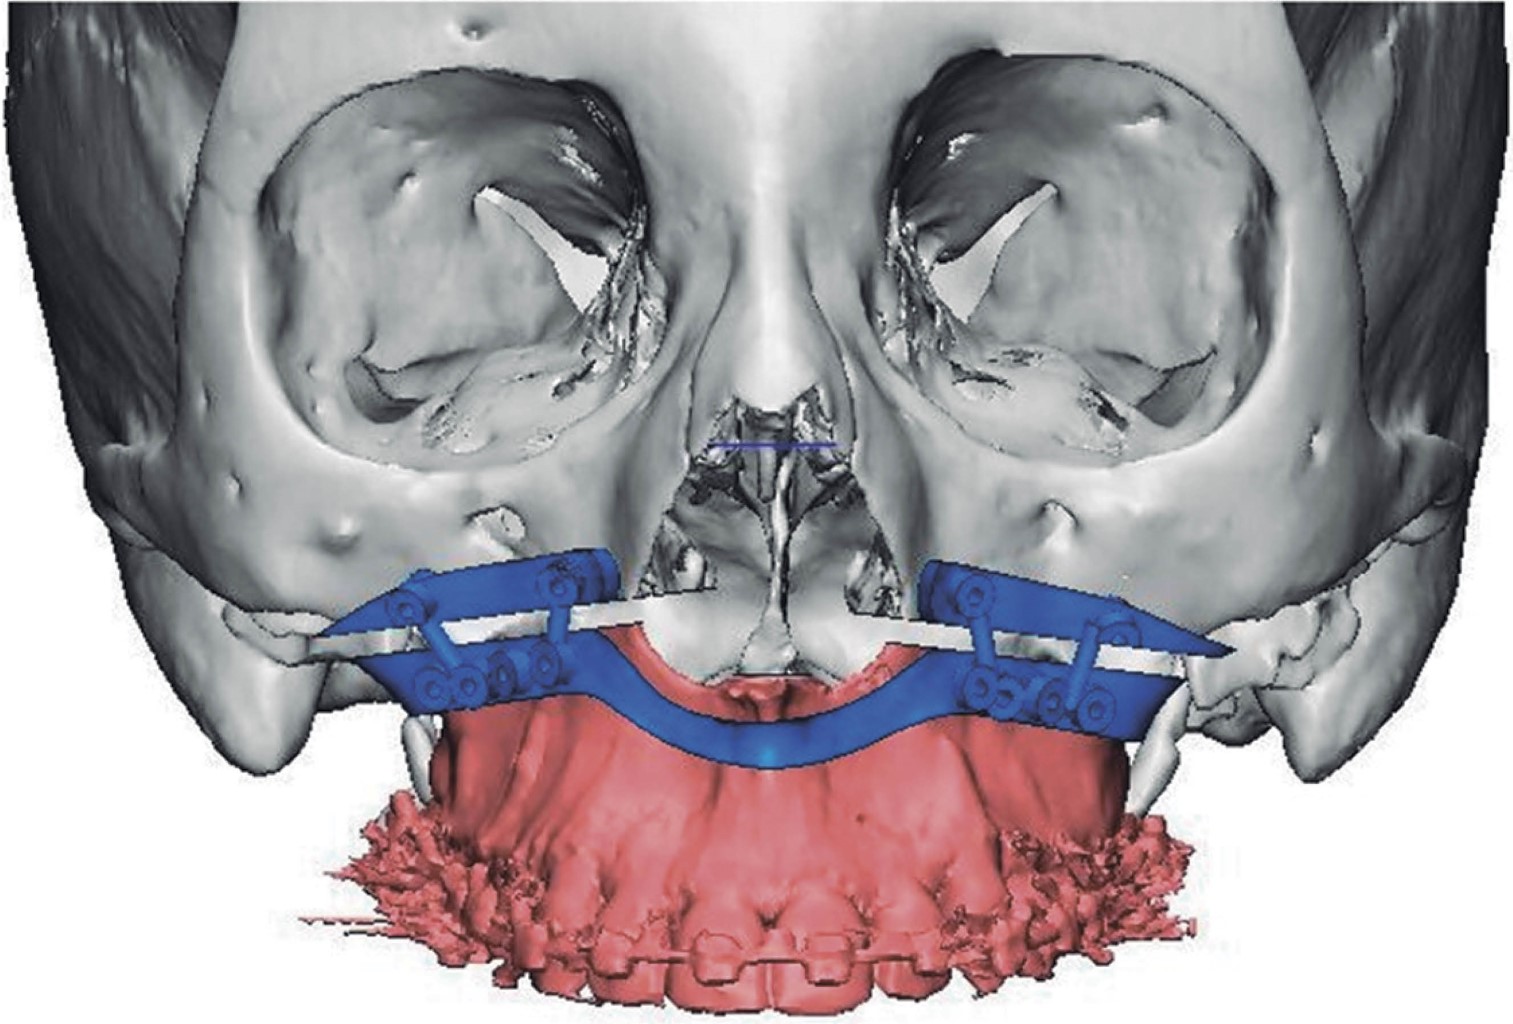

Introduction: currently, computer-aided planning of orthognathic surgery helps us obtain better results, avoiding errors that could occur with conventional orthognathic surgery planning. With virtual planning of orthognathic surgery, we obtain surgical guides that help us stabilize the maxillary segments during surgery to avoid recurrences. Currently, the use of cutting guides and customized plates in Le Fort I osteotomy eliminates the need for occlusal surgical guides, minimizing surgical time, making the surgery more agile, and improving results. Clinical case: a 20-year-old female patient was diagnosed with maxillary vertical excess and anterior open bite. Surgery was performed using virtual surgery to plan a 4 mm Le Fort I impaction osteotomy, using custom-made titanium plates and cutting guides during the procedure. Results: the advantages of using this management protocol in orthognathic surgery are: reducing pre- and intraoperative work time, minimizing errors in surgical movements, developing simpler and more precise surgical procedures, avoiding injuries to the anatomical structures involved, transferring the results of the virtual simulation in the manufacture of cutting templates to the operating room, obtaining highly satisfactory results, carrying out and establishing an optimization protocol and finally obtaining a database of surgical patients. Conclusions: it is a versatile technique, with a minimum degree of difficulty and easy to perform.

Figure 3